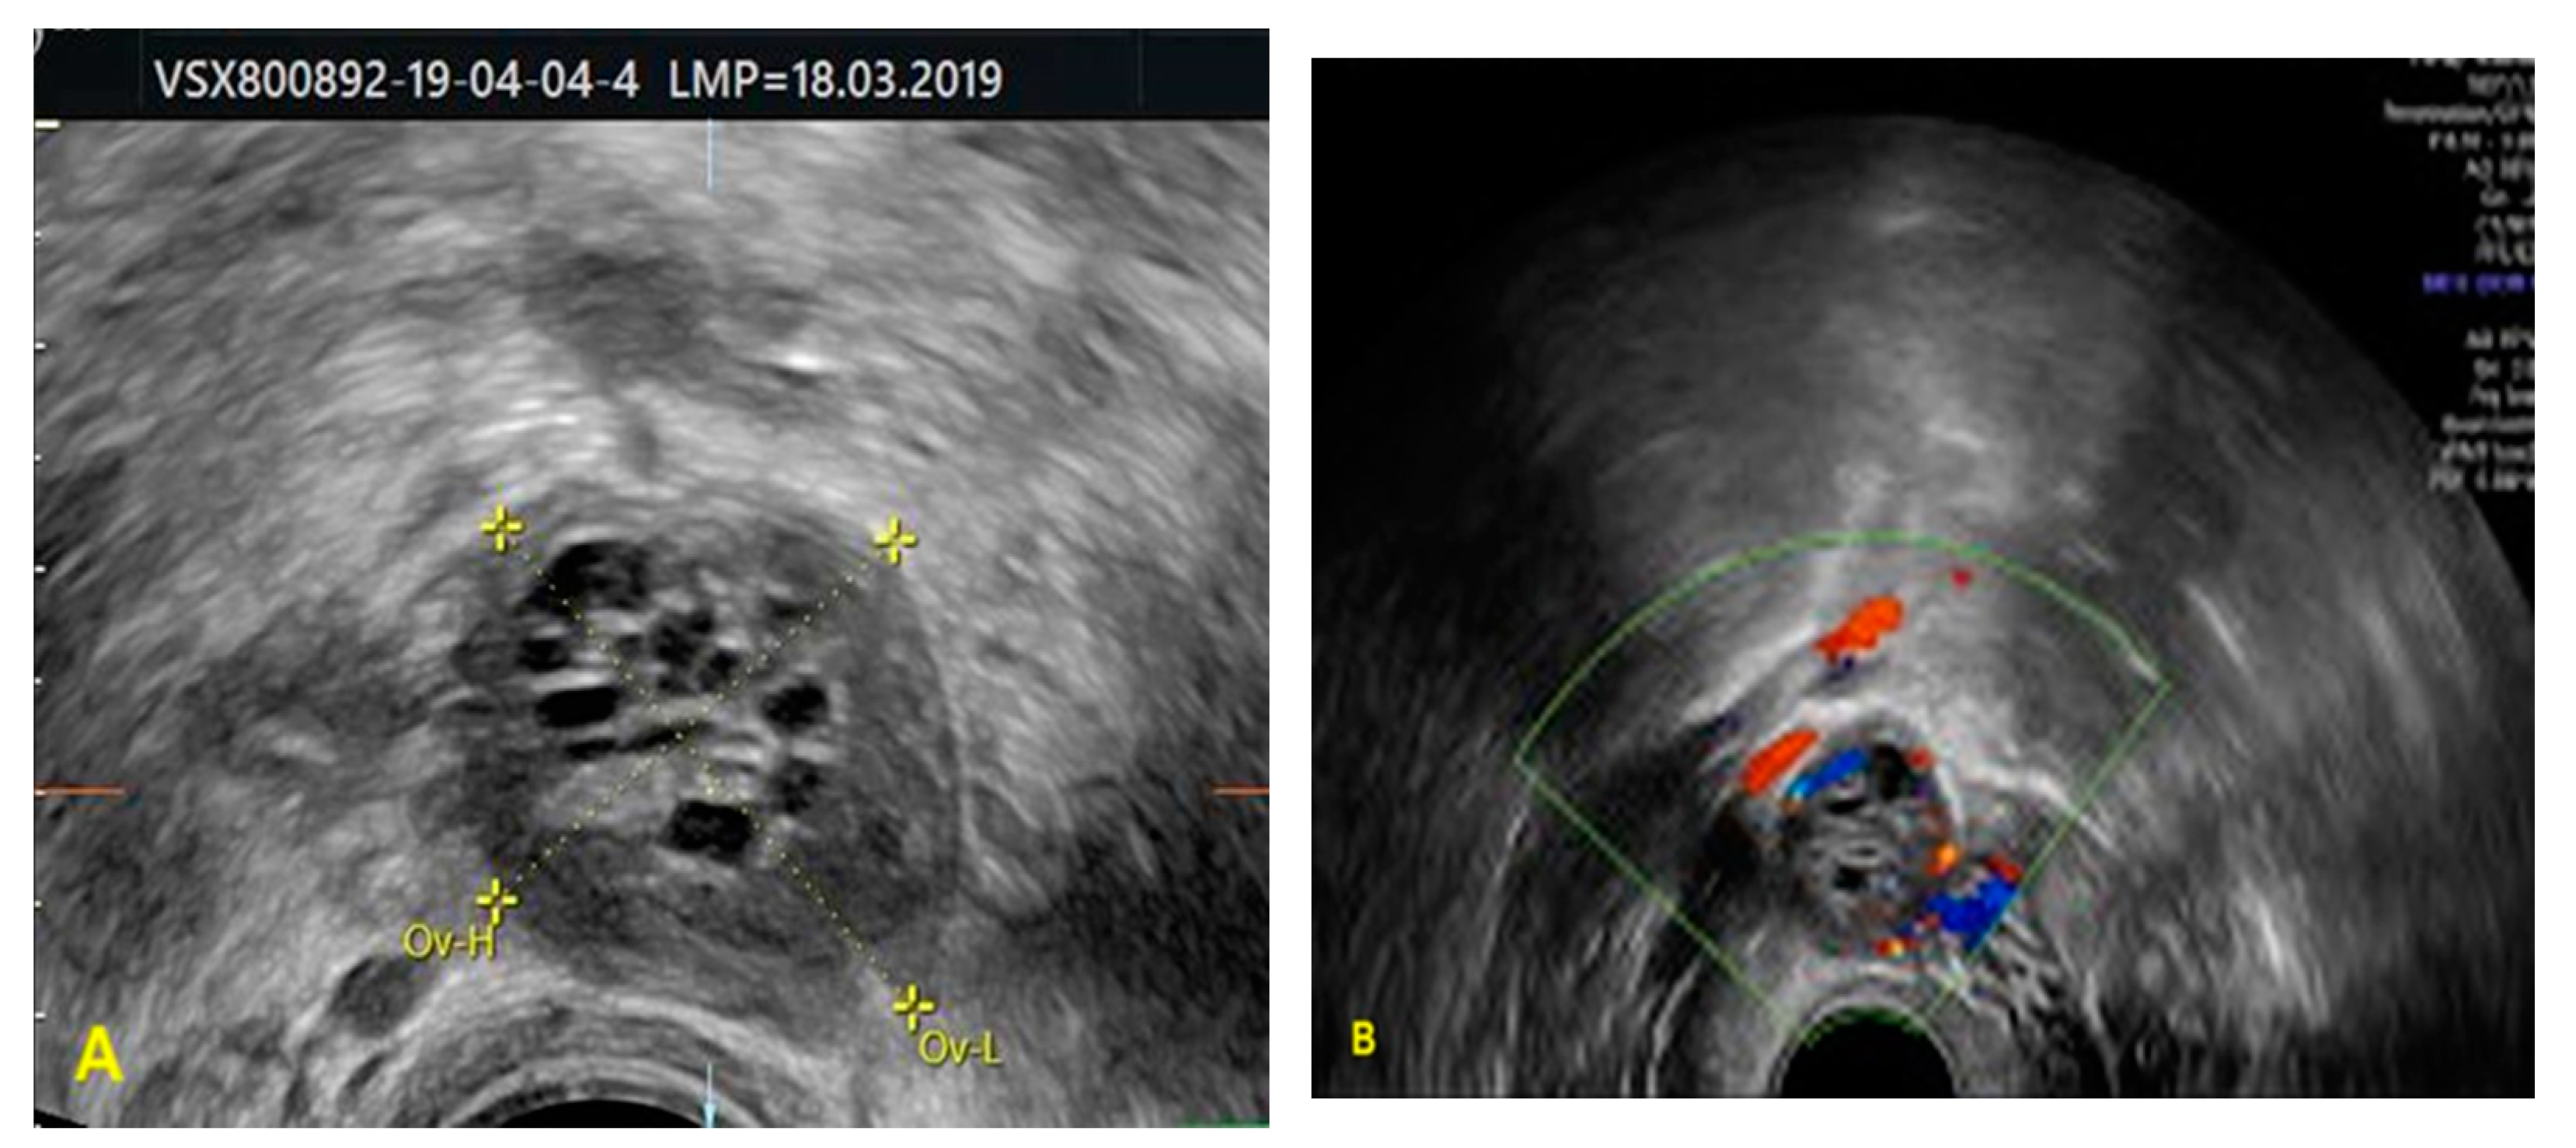

2. Case Report